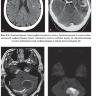

Примеры страниц из книги"Лучевая диагностика при заболеваниях системы крови" - Е. В. Крюкова, Д. В. Давыдова